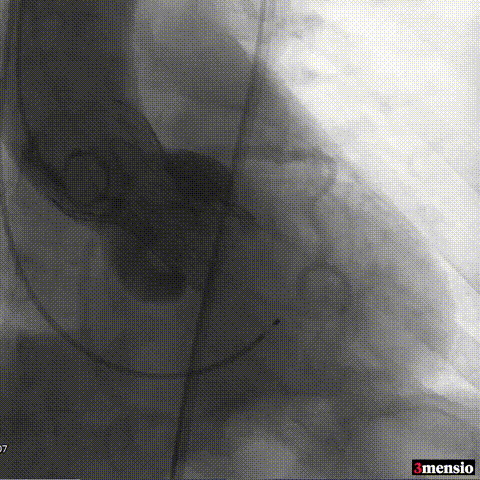

术后即刻评估:

图片

术后压差从66mmHg降至2mmHg,瓣膜正常工作,患者血流动力学即刻得到改善。